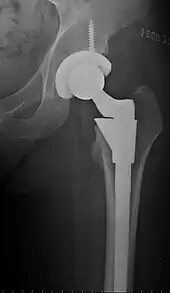

Intraoperative acetabular fracture

Intraoperative fractures may occur. After surgery, bones with internal fixation devices in situ are at risk of periprosthetic fractures at the end of the implant, an area of relative mechanical stress. Post-operative femoral fractures are graded by the Vancouver classification.[31][32]